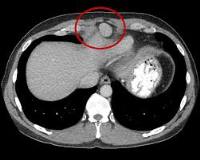

- КТ брюшной полости. Рентгеновская компьютерная томография является предпочтительным методом визуализации с общей чувствительностью 93%, специфичностью 100%. С ее помощью удается выявить билиодигестивную фистулу, определить уровень желчного илеуса, определить состояние желчного пузыря.